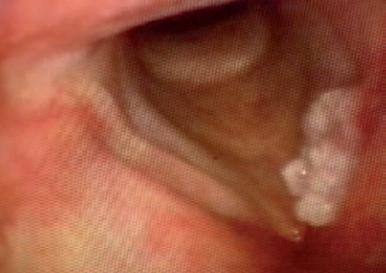

O femeie de 79 de ani COVID+ s-a deplasat la secția de Oftalmologie cu colecție fistulizată în treimea interioară a polului anterior a pleoapei inferioare. Inițierea tratamentul s-a efectuat cu Cefort 1 gr și Gentamicină 80 mg și antiinflamatoare. Examenul CT a evidențiat formarea chistică cu dimensiunile de 2,7/1,5 cm adiacent cantului medial al ochiului stâng cu extensie la nivelul canalului naso-lacrimal cu un calibru crescut. Datorită evoluției staționare s-a cerut consult în serviciul de Otorinolaringologie.

O femeie de 79 de ani s-a internat de urgență în Secția de Oftalmologie cu infecție SARS-CoV-2 pozitivă acuzând: edem periorbitar, cu motilitate oculară păstrată, fără diplopie, fără exoftalmie, fără chemozis, secreții purulente în sacul conjunctival, cornee transparentă, pupila rotundă centrală, iris cu model radial, cataractă corticonucleară, canale lacrimale nepermeabile. Abcesul a fistulizat exterior în treimea interioară a polului anterior al pleoapei inferioare asociind hiperemie și

edem palpebral. Antecedentele heredocolaterale evidențiază un istoric de hipertensiune arterială și un cancer mamar operat radiotratat, care nu a fost relevant pentru strategia de tratament. Se inițiază un tratament antibiotic intravenos cu: Ceftriaxona 1 gr la 12 ore asociat cu Gentamicină 80mg/2ml la 12 ore, tratamentul local a fost asocierea de: Bethametazona și soluție Cloramfenicol (Betabioptal). După 24 de ore de tratament edemul pleoapei este remis dar rămâne un edem eritematos, indurat inferior (din unghiul intern spre treimea externă), fără chemozis, nedureros, mobilitate prezentă, fără diplopie în toate cadranele, restul polului de aspect normal. Pacienta a avut o stare generală bună, afebrilă, fără tulburări de motilitate vizuală și oculară. Nu au fost raportate antecedente traumatisme faciale. S-a efectuat un examen CT cerebral în urma căruia s-a evidențiat o formațiune chistică cu dimensiunile de 2,7/1,5 cm adiacent cantului medial al ochiului stâng cu extensie la nivelul canalului naso-lacrimal arătând un calibru crescut cu o densificare difuză asemănătoare celulitei a țesutului palpebral stâng și cu osteoliză la nivelul laminei papiracee. Pacienta a refuzat tratamentul SARSCoV-2 și, din cauza progresului staționar, a fost trimisă la secția de Otorinolaringologie pentru a doua opinie. Inițial s-a verificat permeabilitatea ductului naso-lacrimal, s-a schimbat tratamentul cu antibiotice Ceftriaxona cu Levofloxacina, s-a practicat o incizie la nivelul orificiului

de fistulizare pentru un drenaj eficient al abcesului urmat de tratament local. Evoluția pacientei a fost favorabilă astfel încât după 4 săptămâni s-a efectuat intervenția endoscopică de dacriocistorinostomie (DCR) pentru evaluarea permeabilității ductului naso-lacrimal. Evoluția după 2 luni de la operație nu a evidențiat recidiva abcesului iar permeabilitatea ductului a fost restabilită.